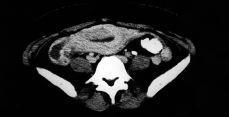

Figura 2. AngioRMN en la que se observa la trombosis de la vena ovárica derecha en su confluencia con la vena cava inferior.

A las 48 horas del primer TAC, e iniciado el tratamiento anticoagulante, la paciente presentó dolor en fosa lumbar derecha que irradia a FID, por lo que se practicó nuevo TAC y una angioRMN en los que se visualiza un discreto aumento en el volumen del trombo en VCI y en el componente de ectasia del uréter derecho, explicable por la relación anatómica entre éste y la vena ovárica trombosada. Se aumentan las dosis de heparina sódica a 26.000 UI/24h y se modifica la pauta antibiótica: cefotaxima, clindamicina y doxiciclina, remitiendo el cuadro álgico y febril a los cuatro días del inicio de este tratamiento.